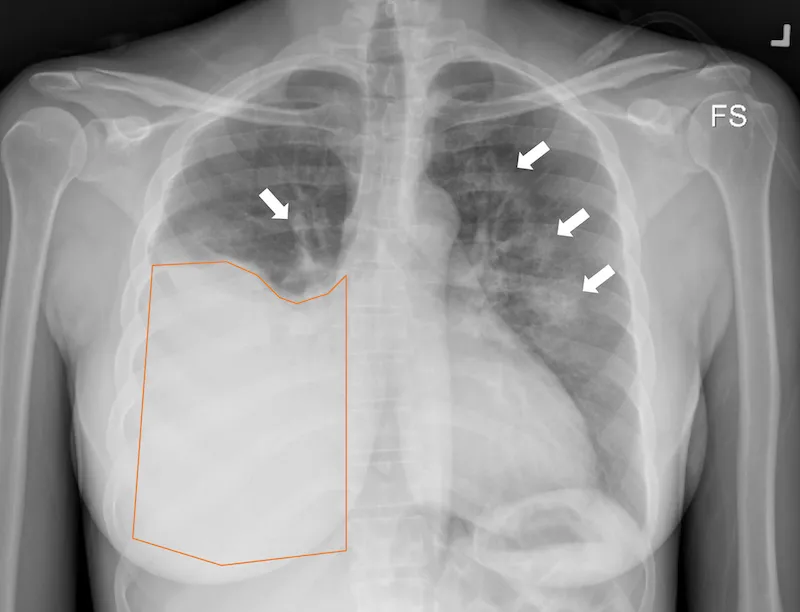

- Chylothorax: Lymph (chyle) accumulation in the pleural space, often from thoracic duct injury.

- Causes: Thoracic surgery (e.g., esophagectomy), chest trauma, mediastinal tumors (lymphoma).

- Presentation: Dyspnea, cough. Fluid analysis reveals a milky, opalescent appearance.

⭐ Exam Favorite: A chylothorax is confirmed via thoracentesis. The key diagnostic finding is a pleural fluid triglyceride level > 110 mg/dL.